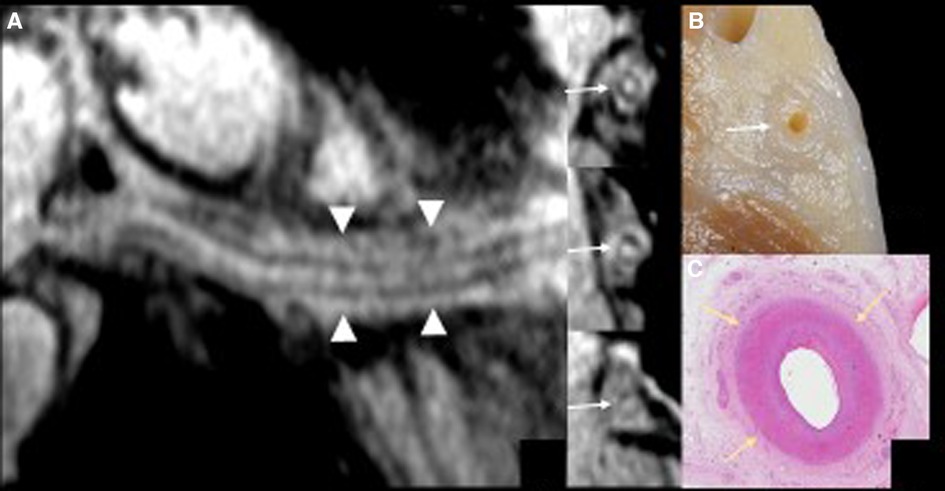

Figure 3. The curved multiplanar reformatting view (panel A) of the right coronary artery with the 3 short-axis vessel views using high resolution magnetic resonance (MR) coronary imaging with additional fat epicardial suppression (whole-heart imaging) confirms wall thickening along the course of the right coronary artery (arrows) and inflammatory abnormalities of the epicardial fat surrounding the vessel (arrowheads). The detailed anatomical view of the right atrioventricular groove (panel B) matches the MR coronary findings.

A 29-year-old female heart transplant recipient presented to our care center with a generalized poor health condition. The patient was affected by congenitally corrected transposition of the great arteries with a subpulmonary interventricular defect and right ventricular hypoplasia. In 1998 at the age of twelve the patient underwent Glenn atrial switch procedure. In September 2015, heart transplantation was performed for severe heart failure refractory to therapy and episodes of paroxysmal supraventricular tachycardia that required frequent hospitalization. Due to residual claudication caused by severely impaired lower limb muscles, the patient was unable to undergo a stress test during periodical follow-up or during hospitalization. Upon admission to our care center, the patient appeared pale and complained of dizziness and fatigue. The patient's blood pressure was 123/70 mmHg with a heart rate of 105 beats/min. The 12-lead electrocardiogram (ECG) showed sinus tachycardia, first degree atrioventricular block, right bundle branch block, and diffuse non-specific abnormalities of ventricular repolarization. Transthoracic echocardiography revealed a slightly reduced left ventricular ejection fraction (46%). Laboratory findings showed a normal cardiac troponin I level (5.4 pg/ml) and an elevated terminal pro brain type natriuretic peptide level (353 pg/ml). Invasive coronary angiography showed severe stenosis at the distal portion of the circumflex coronary artery and diffuse sclerosis of the left anterior descending coronary artery. Intravascular ultrasonography showed a Stanford scale IV score (Figure 1). Consequently, the therapeutic strategy was revised and low-dose bisoprolol, ace inhibitors, and diuretics were added to the remaining medication, which comprised cyclosporine, everolimus, pravastatin, and aspirin. At day 7 of hospitalization echocardiography showed improvement of the left ventricular function (58%) and a reduction of the N-terminal pro brain type natriuretic peptide level (235 pg/ml). The symptoms disappeared and the patient was discharged with a scheduled CMRI 7 days later. CMRI was performed using a 1.5 Tesla scanner (Magnetom Aera 1.5 T; Siemens, Erlangen, Germany) and showed mild concentric hypertrophy of the left ventricle and moderately reduced left ventricular function. T2-weighted short-tau inversion recovery (STIR) sequence images showed widespread sub-epicardial hyperintensity of the myocardial segments (signal intensity ratio to skeletal muscle > 2) along the course of the coronary arteries (Figure 2). T2 mapping sequences showed an elevated value of 57 ms, and the myocardial native T1 values and extracellular volume percentage were significantly elevated (1170 ms and 41%, respectively). Late gadolinium enhancement (0.2 mmol/kg Gadoteric Acid, Dotarem®, Guerbet, France) demonstrated diffuse sub-epicardial hypersignal along the lateral, free, and left ventricular walls. The “whole-heart” sequence (navigator-gated, vector ECG-triggered, fat-suppressed T2-weighted 3-dimensional gradient-echo inversion recovery) demonstrated widespread hyper-enhancement of epicardial fat along the course of the thickened main coronary artery walls (Figure 3) At rest, there were no sub-endocardial defects in the anteroseptal and basal infero-septal segments. Fifteen days after the CMRI was performed, the patient experienced an episode of lipothymia at home and was re-admitted through the emergency department. Due to the rapid and progressive worsening of the patient's clinical condition, which included severe hypotension and the need of inotropic drugs, the patient was placed on the transplant waiting list and underwent re-transplantation in May 2017. At the last follow-up, the patient was in a good condition and will be continuously followed at our dedicated heart transplant clinic.

CMR imaging-based myocardial tissue characterization with T1 and T2 mapping has emerged as a non-invasive and highly sensitive method of detecting cardiac allograft rejection, with numerous studies demonstrating good correlation between CMR-based mapping and histopathology-determined rejection (1). A single CMRI study can provide information on cardiac volumes, function, wall motion, tissue characterization, and ischemia at rest, pharmacological stress testing, and myocardial perfusion reserve assessment, which is an important prognostic factor in the evaluation of heart transplant recipients. CMRI can also identify edema, which is often associated with acute heart transplant rejection or myocarditis. Strategies to detect myocardial edema include semi-quantitative measures, such as T2 signal intensity ratios, or quantitative techniques, such as T2 mapping (2, 3). CMR imaging-based myocardial tissue characterization with late enhancement sequences (4) and sequences such as T1 and T2 mapping has emerged as a non-invasive and highly sensitive method of detecting cardiac allograft rejection. Numerous studies demonstrated good correlation between CMR-based mapping and histopathology-determined rejection (1). In our case, CMRI showed non-specific elevation of inflammatory indices, increased T2 mapping values (Figure 4), and widespread sub-epicardial hyperintensity along the course of the coronary arteries on STIR sequences (Figure 3). We observed an impressive correlation between CMRI, invasive coronary angiography images, and increased endocardial fibrosis of the circumflex coronary and left anterior descending arteries in the explanted heart (5). Interstitial inflammatory cellularity along the course of the coronary arteries correlated with the CMRI images; however, it was not detectable on the invasive coronary angiography images (Figure 1). Some authors have described the importance of the myocardial perfusion reserve (MPR) index as the only parameter able to independently predict microvascular and macrovascular CAV (3, 6). In our young girl recipient, it was not possible to estimate MPR because of her worsening clinical condition. However, first-pass perfusion imaging performed on the patient at rest did not demonstrate subendocardial defects. At late enhancement sequences, our patient did not show the typical pattern of late gadolinium enhancement, usually related to severe CAV on angiography, as some studies described (3, 7). However, we found an unusual extensive hyperenhancement of epicardial fat along the course of the main coronary arteries and diffuse subepicardial enhancement with a corresponding diffuse edema (Figure 3). In addition, myocardial T1 mapping showed elevation of native T1 mapping and ECV (Figure 4), providing a quantitative measurement of extracellular volume expansion such as a more sensitive marker of adverse change within the cardiac allograft. Examination of explanted heart showed distal branches of main subepicardial coronary arteries and small peripheral vessels characterized by severe intimal proliferation, sometime till complete obliteration of the lumen (Figure 5) without necrosis, calcification and cholesterol cleft, with an intact internal elastic lamina (Figure 6) these findings are consistent to the CAV demonstrated by coronary angiography. No myocardial infarction or diffuse interstitial scarring was evident, particularly along the coronary arteries, owing to perivascular fibrous tissue being poorly vascularized and focally infiltrated by sparse mononuclear cells. These findings could be related to the development of acute perivascular inflammation, which was probably immune-mediated before intimal proliferation and, therefore, before the sequelae of myocardial scarring occurred. Existing methods for monitoring the allograft are invasive and may be insufficiently sensitive. Advanced methods, such as CMRI, may be routinely utilized to evaluate cardiac allograft vasculopathy progression and help to define the best immunosuppressive protocol strategy.